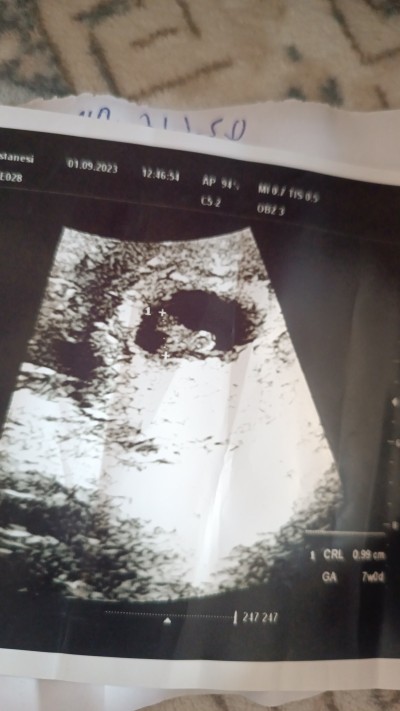

Kızlar bakarmisnz bebeğimin kesesi sagdami soldami

image

Gebelik haftası 8

Bebeğin solda duruyor erkek gibi geldi cinsiyet olarak

Canım aslında muayene de kendin de hissedersin ultrason cihazını sağ sol görebilirsin